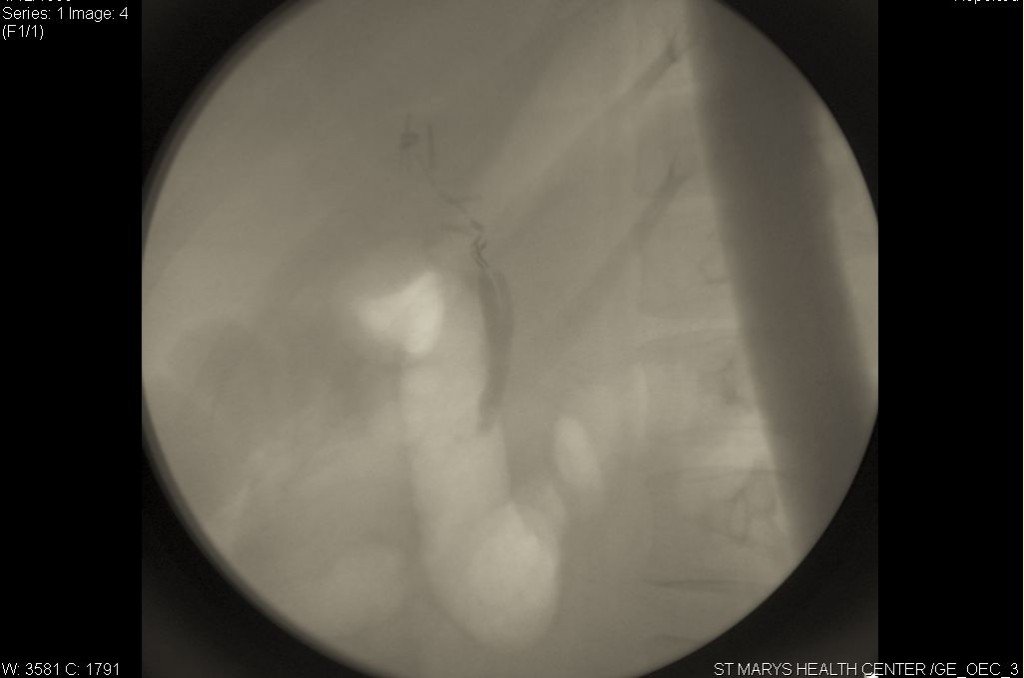

From www.missourilawyers.com

Surgical Clips Left On Common Bile Duct By Missouri Surgeon Why Are Surgical Clips Left In  The mammo came back ok, but was told there was a clip left in that should have been removed at the time of my lumpectomy a year before. Data regarding surgical clip placement and radiation planning in lumpectomy cavities are emerging, and evidence suggests a. I only found out that i had clips left in when i had to go. Why Are Surgical Clips Left In.